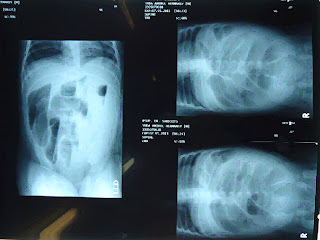

Kemudian, dilakukan pemeriksaan foto abdomen 3 posisi dan juga USG abdomen

Abdomen 3 posisi, didapatkan hasil, tanda-tanda obstruksi usus halus dengan adanya air-fluid level dan udara usus tidak tampak sampai ke kavum pelvis.